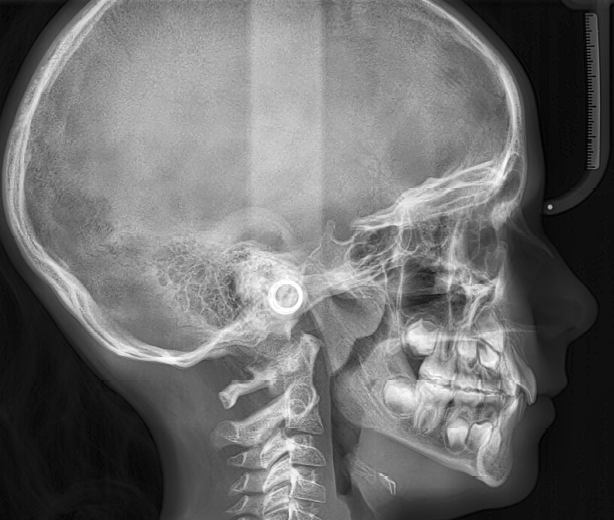

The patient presented with a skeletal Class I relationship and a mesofacial growth pattern, indicating balanced sagittal and vertical skeletal proportions. Dental examination revealed a Class I molar and canine relationship bilaterally. The patient was in the mixed dentition phase. Significant dental crowding was observed in both arches, consistent with a dentoalveolar discrepancy. Midline deviations were present, affecting dental symmetry and occlusal harmony. The maxillary lateral incisors were in crossbite, contributing to anterior transverse discrepancy and functional imbalance.

Periodontal evaluation revealed early signs of periodontal disease, primarily affecting tooth 41. Radiographic assessment demonstrated root convergence of teeth 11 and 21, indicating compromised root parallelism. Overall, the initial presentation was characterized by dentoalveolar crowding, transverse discrepancies, occlusal asymmetries, and early periodontal involvement within an otherwise favorable skeletal framework, requiring a carefully planned orthodontic approach to ensure functional stability and periodontal preservation.